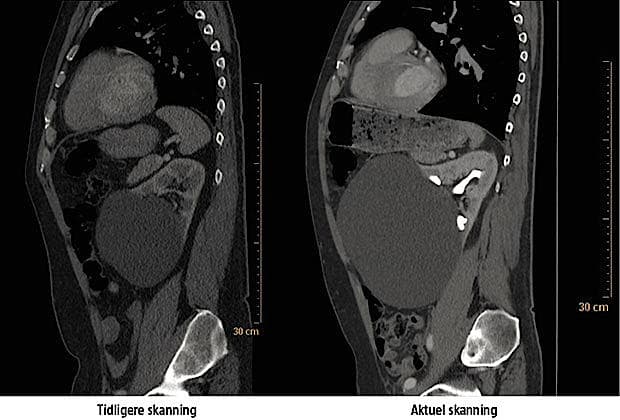

En 59-årig mand med dilateret aorta ascendens, mekanisk aotaklap og hypertension blev indlagt akut med smerter under venstre skulderblad. Han havde gennem flere måneder være plaget af træthed, synkebesvær, opkastninger, 5-6 natlige opvågninger med svedeture og uro, smerter i maven, begge ben, balder og lænderyg samt skiftende afføringsmønstre. Han havde ikke åndenød eller vandladningssymptomer. Ved undersøgelser fandt man normalt ekg, ekkokardiografi med en uddrivningsfraktion på > 70%, koronare iskæmimarkører i normalområdet og upåfaldende biokemi. En CT viste ingen progression af aortadilatationen, men størrelsestilvækst af en simpel venstresidig nyrecyste fra 6 cm fem år tidligere til nu 19 cm i diameter. Ved en ultralydvejledt aspiration blev der udtømt tre liter klar cystevæske. Tre uger senere kunne patienten fortælle om »et helt nyt liv«, hvor smerterne var fuldstændig forsvundet, fødeindtag og afføringsmønster normaliseret og nattesøvnen uafbrudt. Der blev planlagt en laparoskopisk masupialisering af cystesækken.